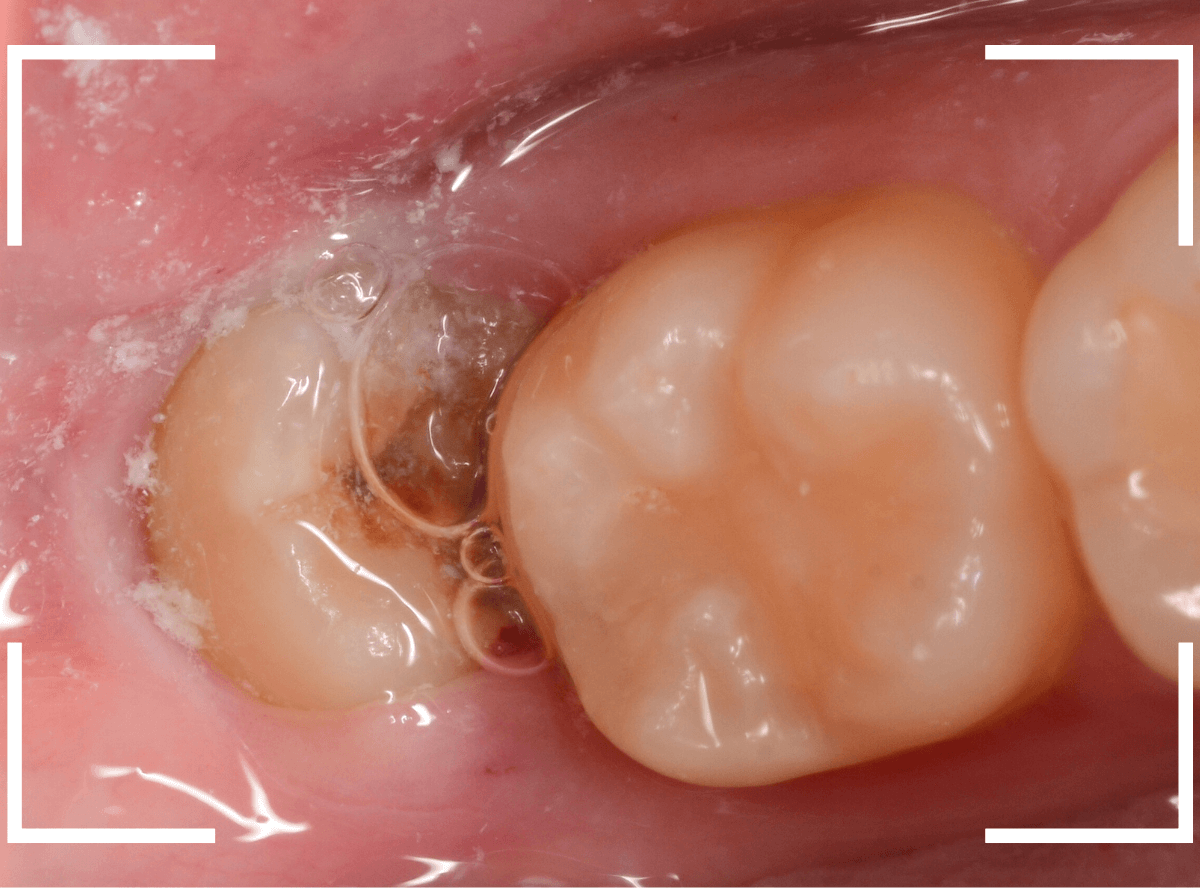

このようなおやしらず、あなたはありませんか?